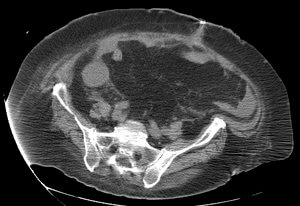

23 year old female with fever and RLQ tenderness s/p appendectomy.

Comment: This case demonstrates performance of a straight-forward CT-guided drainage. Once the abscess was localized on CT and the access site confirmed with a 25g needle, the collection was accessed with a Chiba needle and a guidewire was coiled within the collection. Serial dilatation was then performed so that a pigtail drainage catheter could be placed within the collection for drainage.